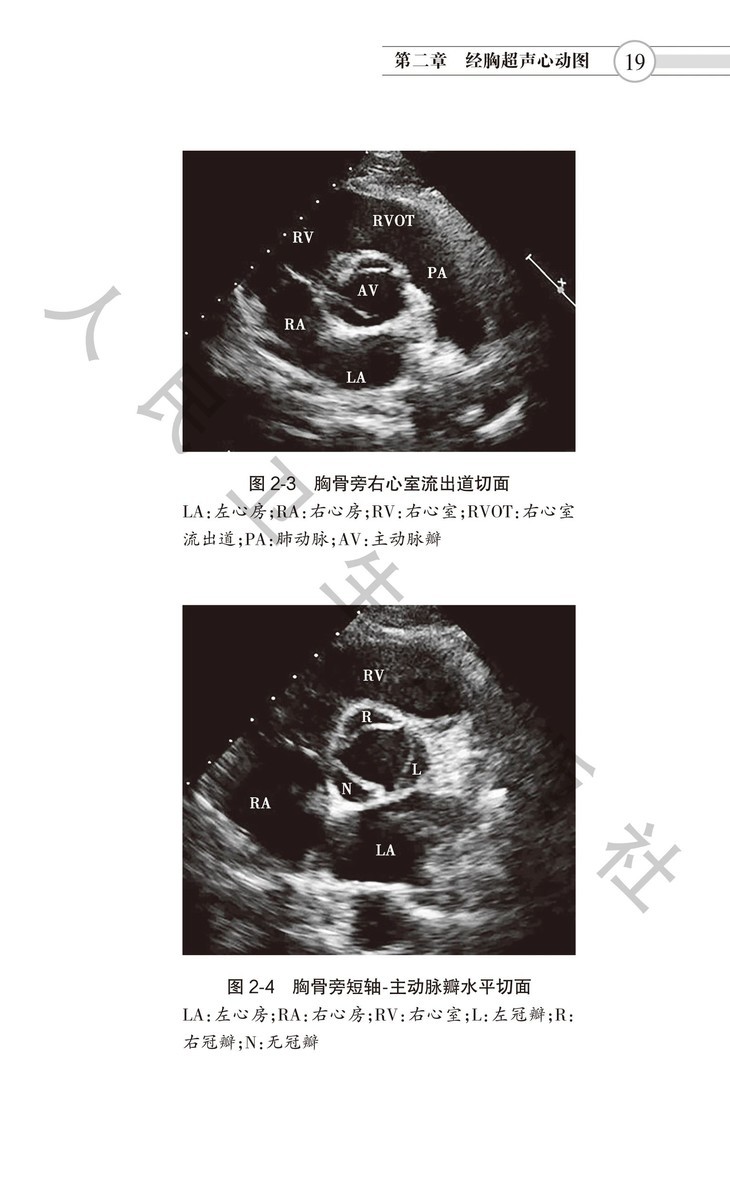

本书是中国医师协会超声医师分会组织编写,邀请众多国内一流心脏超声专家参与、研究和讨论,在2016年出版的《超声心动图检查指南》基础上修订而成。本指南分为七章。涵盖经胸超声、经食管超声、右心造影、负荷超声、床旁超声心动图等各类技术,尤其是超声心动图在各种常见心血管疾病诊断中的应用。涉及超声心动图检查适应证、禁忌证、 检查要点、注意事项和超声报告结论须涵盖内容等,旨在规范超声医师检查行为,适合各年资医师学习阅读,是指导超声医师临床工作的规范性用书。